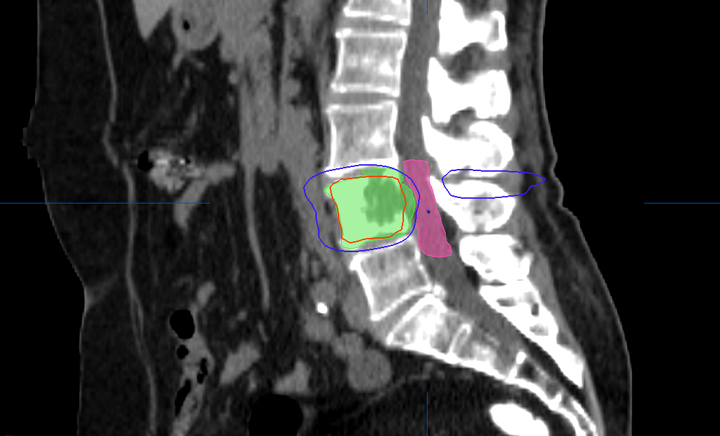

El 40% de los pacientes tuvo reducción del dolor y mejor calidad de vida a los 10 días de iniciar el tratamiento. Se debe ofrecer radioterapia para las metástasis óseas a todos los pacientes, incluso a aquellos con una supervivencia pobre. JAMA Oncology, 9 de febrero de 2017